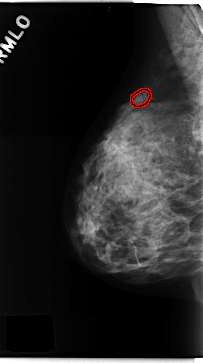

C_0167_1.RIGHT_MLO

RIGHT_MLO LINES 4712 PIXELS_PER_LINE 2632 BITS_PER_PIXEL 12 RESOLUTION 50 OVERLAY

FILE: C_0167_1.RIGHT_MLO.OVERLAY

TOTAL_ABNORMALITIES 1

ABNORMALITY 1

LESION_TYPE CALCIFICATION TYPE PLEOMORPHIC DISTRIBUTION CLUSTERED

ASSESSMENT 5

SUBTLETY 5

PATHOLOGY MALIGNANT

TOTAL_OUTLINES 1

BOUNDARY